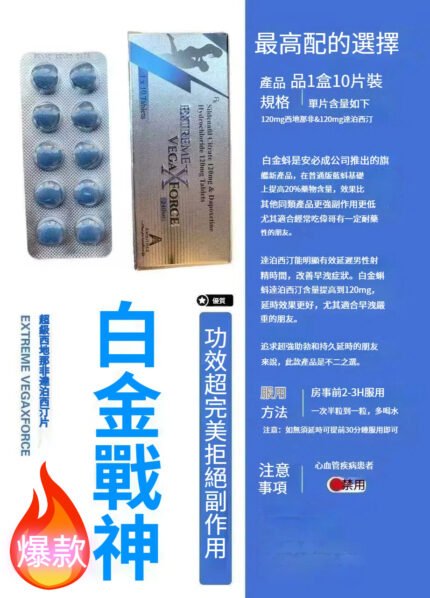

最強雙效超級威爾剛Stenagra Super power超級紫蝌蚪必利勁威猛雙效片10粒/盒|西地那非150mg+達泊西丁100

2025新版上市三效威而鋼黑鑽 C200

5倍時長,5倍硬度

一顆頂5顆,久戰不軟

速效勃起,持久監聽

堅如磐石,硬如鋼鐵

週年慶全館最低65折,2023三效威而鋼黑鑽新品價格史低!下單的朋友想要了解更多產品請點擊下方鏈接進行選購,全部保證是正品有效,百分百有效,沒有效果不要錢.

想不想更持久,想不想一夜來3次,每次都達到1個小時以上?

簡單方便,約會只需帶一片

5分鐘就可見效

1080名志願者服用一個月新型三效威而鋼黑鑽未出現任何副作用,無一有臉部泛紅、頭痛、視力異常等副作用

1080名志願者都能在15分鐘內快速勃起,達到最堅硬的狀態,成功率100%;

1080名志願者的平均性愛時長達到了49.7分鐘,平均增加36.5分鐘,最長的時長達到了151.9分鐘;